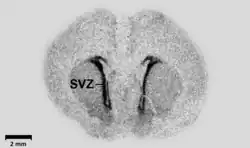

GABA nu poate traversa bariera hematoencefalică (în afara anumitor zone ale creierului, unde această barieră nu este efectivă, precum nucleul periventricular), aceasta fiind sintetizată in vivo.